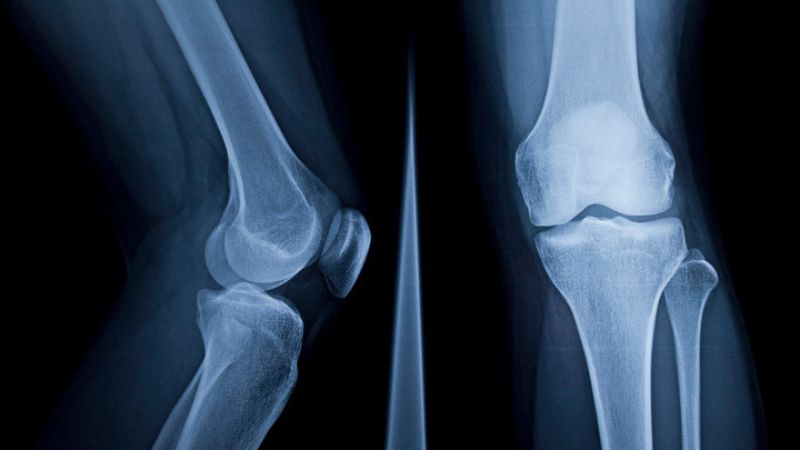

Về cơ bản, các gai này đã hình thành từ giai đoạn đầu của thoái hóa khớp gối nhưng không gây đau đớn. Thông thường, bệnh nhân chỉ cảm nhận được các triệu chứng đầu tiên khi các gai xương này lớn lên, cọ xát vào mô mềm, dây chằng, hoặc sụn, gây đau và hạn chế vận động. Khi được chẩn đoán, đa số người bệnh đã bị gai xương ở giai đoạn 2, 3, thậm chí phát hiện biến chứng biến dạng đầu xương ở phim chụp giai đoạn 4.

Khớp gối bị gai xương dưới hình chụp X Quang

Đa số các tổn thương ở gai xương được phát hiện dưới phim chụp X Quang và sau khi bác sĩ kiểm tra biên độ vận động của khớp gối. Trong trường hợp phát hiện gai xương lớn hoặc bệnh nhân có tiền sử bệnh lý phức tạp, bạn có thể được bác sĩ chỉ định chụp CT hoặc chụp MRI để đánh giá chuyên sâu sự tổn thương về mặt cấu trúc và các mô mềm, các bộ phận xung quanh có bị ảnh hưởng không.